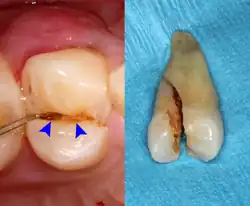

Lateral periodontal abscess (blue arrows) due to a fracture (green arrows)

A periodontal abscess (lateral abscess) is a collection of pus that forms in the gingival crevices, usually as a result of chronic periodontitis where the pockets are pathologically deepened greater than 3mm. A healthy gingival pocket will contain bacteria and some calculus kept in check by the immune system. As the pocket deepens, the balance is disrupted, and an acute inflammatory response results, forming pus. The debris and swelling then disrupt the normal flow of fluids into and out of the pocket, rapidly accelerating the inflammatory cycle. Larger pockets also have a greater likelihood of collecting food debris, creating additional sources of infection.[21]: 443

Periodontal abscesses are less common than apical abscesses, but are still frequent. The key difference between the two is that the pulp of the tooth tends to be alive, and will respond normally to pulp tests. However, an untreated periodontal abscess may still cause the pulp to die if it reaches the tooth apex in a periodontic-endodontic lesion. A periodontal abscess can occur as the result of tooth fracture, food packing into a periodontal pocket (with poorly shaped fillings), calculus build-up, and lowered immune responses (such as in diabetes). Periodontal abscess can also occur after periodontal scaling, which causes the gums to tighten around the teeth and trap debris in the pocket.[21]: 444–445  Toothache caused by a periodontal abscess is generally deep and throbbing. The oral mucosa covering an early periodontal abscess appears erythematous (red), swollen, shiny, and painful to touch.[22]